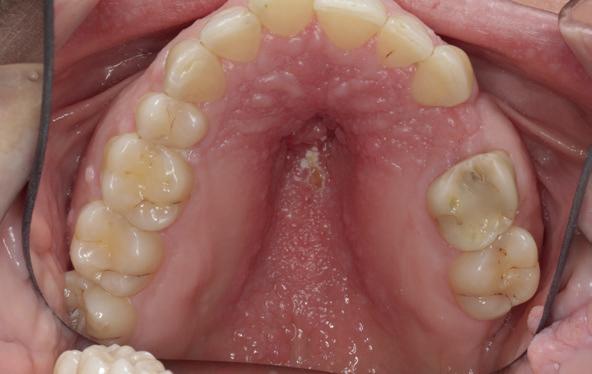

Voor het implantologisch onderzoek werd een CBCTscan (Trium CBCT, Acteon Frankrijk) vervaardigd van de edentate bovenkaak en in de software werd een planning gemaakt van 6 implantaten in de bovenkaak. De kaak kan opgedeeld worden in het front, tussen de 13 en 23 en de zijdelingse delen van de 14 t/m 17 en 24 t/m 27. Er dienen 2 implantaten in het front geplaatst te worden en 2 implantaten in de zijdelingse delen rechts en links, om een optimale verdeling van de implantaten (implant spread) te krijgen. De implantaten in deze casus werden gepland op posities 12, 22, 14, 24, 16 en 27. Tevens werd rekening gehouden met de krachtenverdeling óp de implantaten, deze zijn naar dorsaal toe forser dan in het front, daarom werd er gekozen voor brede implantaten (meer dan 5.0 mm in diameter) distaal en 4.0 mm diameter implantaten in het front. Voor de 16 was een crestale sinusbodemelevatie nodig en de 14 benodigde een kaakverbreding en verhoging.

Om de implantaten op de juiste vooraf geplande positie te implanteren, zijn er een aantal mogelijkheden (afbeelding 1 en 2). Eén daarvan is om de chirurgie guided uit te voeren, maar dat is lastig omdat de guide niet op elementen afgesteund kan worden. De guide dient dan met guide pins vastgeschroefd te worden, maar dat heeft als nadeel dat bij verplaatsing van de guide de implantaten niet op de juiste positie staan. Bij immediaat implanteren kan tegenwoordig gebruikgemaakt worden van meerdere stac-

1. Edentate maxilla

2. Planning in de CBCT-software Acteon AIS

kable guides, die op een base guide geklikt kunnen worden. Een tweede methode is om op basis van de CBCT-scan in de mond uit te meten waar de implantaat locaties zijn en door te kijken naar referentie van de onderkaak. In deze cases werd besloten om de implantaten vrij uit de hand te plaatsen.